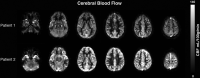

Background and purpose: Children with sickle cell disease have low hematocrit and elevated CBF, the latter of which can be assessed with arterial spin-labeling MR imaging. Quantitative CBF values are obtained by using an estimation of the longitudinal relaxation time of blood (T1blood). Because T1blood depends on hematocrit in healthy individuals, we investigated the importance of measuring T1blood in vivo with MR imaging versus calculating it from hematocrit or assuming an adult fixed value recommended by the literature, hypothesizing that measured T1blood would be the most suited for CBF quantification in children with sickle cell disease.

Materials and methods: Four approaches for T1blood estimation were investigated in 39 patients with sickle cell disease and subsequently used in the CBF quantification from arterial spin-labeling MR imaging. First, we used 1650 ms as recommended by the literature (T1blood-fixed); second, T1blood calculated from hematocrit measured in patients (T1blood-hematocrit); third, T1blood measured in vivo with a Look-Locker MR imaging sequence (T1blood-measured); and finally, a mean value from T1blood measured in this study in children with sickle cell disease (T1blood-sickle cell disease). Quantitative flow measurements acquired with phase-contrast MR imaging served as reference values for CBF.

Results: T1blood-measured (1818 ± 107 ms) was higher than the literature recommended value of 1650 ms, was significantly lower than T1blood-hematocrit (2058 ± 123 ms, P < .001), and, most interesting, did not correlate with hematocrit measurements. Use of either T1blood-measured or T1blood-sickle cell disease provided the best agreement on CBF between arterial-spin labeling and phase-contrast MR imaging reference values.

Conclusions: This work advocates the use of patient-specific measured T1blood or a standardized value (1818 ms) in the quantification of CBF from arterial spin-labeling in children with SCD.